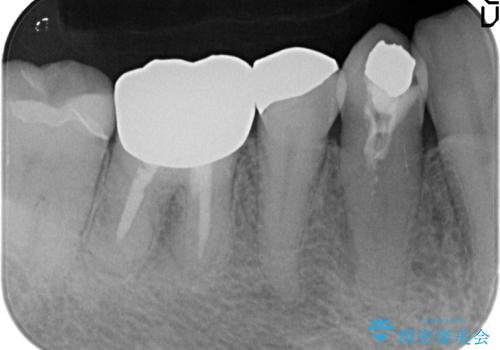

- 他院にて右下4番目の歯の再根管治療が必要だと言われた方の症例です。

再根管治療終了後、オールセラミッククラウンによる補綴を行いました。